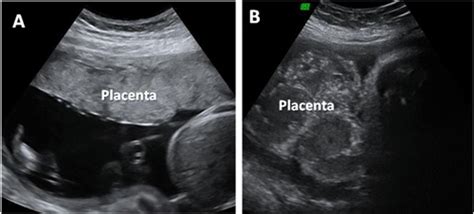

La placenta è un organo vitale che nutre il feto e facilita gli scambi di sostanze attraverso il cordone ombelicale. Normalmente, durante i primi tre mesi di gestazione, la placenta si localizza nella parte inferiore o laterale dell'utero. Con l'avanzare della gravidanza e la crescita del bambino, la placenta tende a spostarsi verso l'alto. Tuttavia, in rari casi, questa migrazione non avviene, dando origine a una condizione nota come placenta previa.

La diagnosi di placenta previa viene generalmente effettuata tra la 25ª e la 26ª settimana di gestazione, sebbene in alcuni casi il quadro ecografico possa essere chiaro anche in epoche precedenti. La dottoressa Tania, alla 24ª settimana di gravidanza, ha ricevuto una diagnosi di placenta previa posteriore, accompagnata da un aumento della pulsatilità delle arterie uterine. Questa condizione, unitamente alla presenza di una cisti ovarica di 3 cm di natura endometriosica, ha sollevato interrogativi sulla progressione della sua gravidanza e sulle precauzioni da adottare.